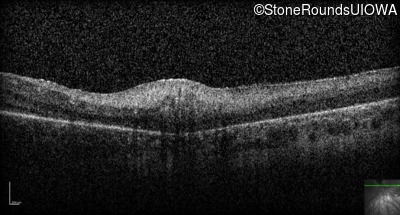

Optical Coherence Tomography - Right -

Light Perception

Exemplar

Optical Coherence Tomography - Left -